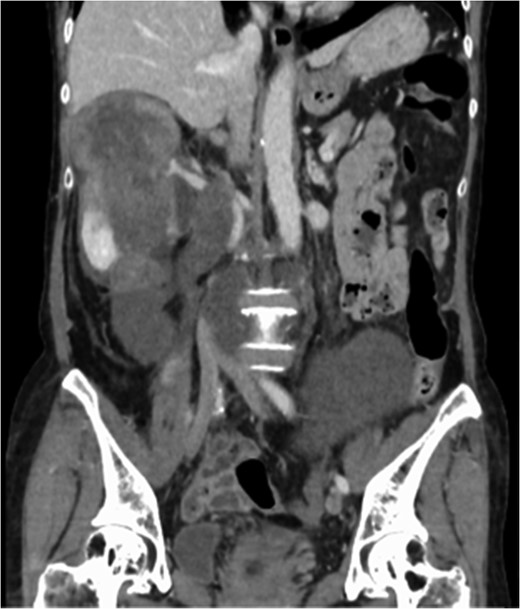

Multidetector CT scan (coronal view and sagittal view). The tumor surrounded the abdominal aorta from the superior mesenteric artery orifice to the common iliac artery bifurcation.